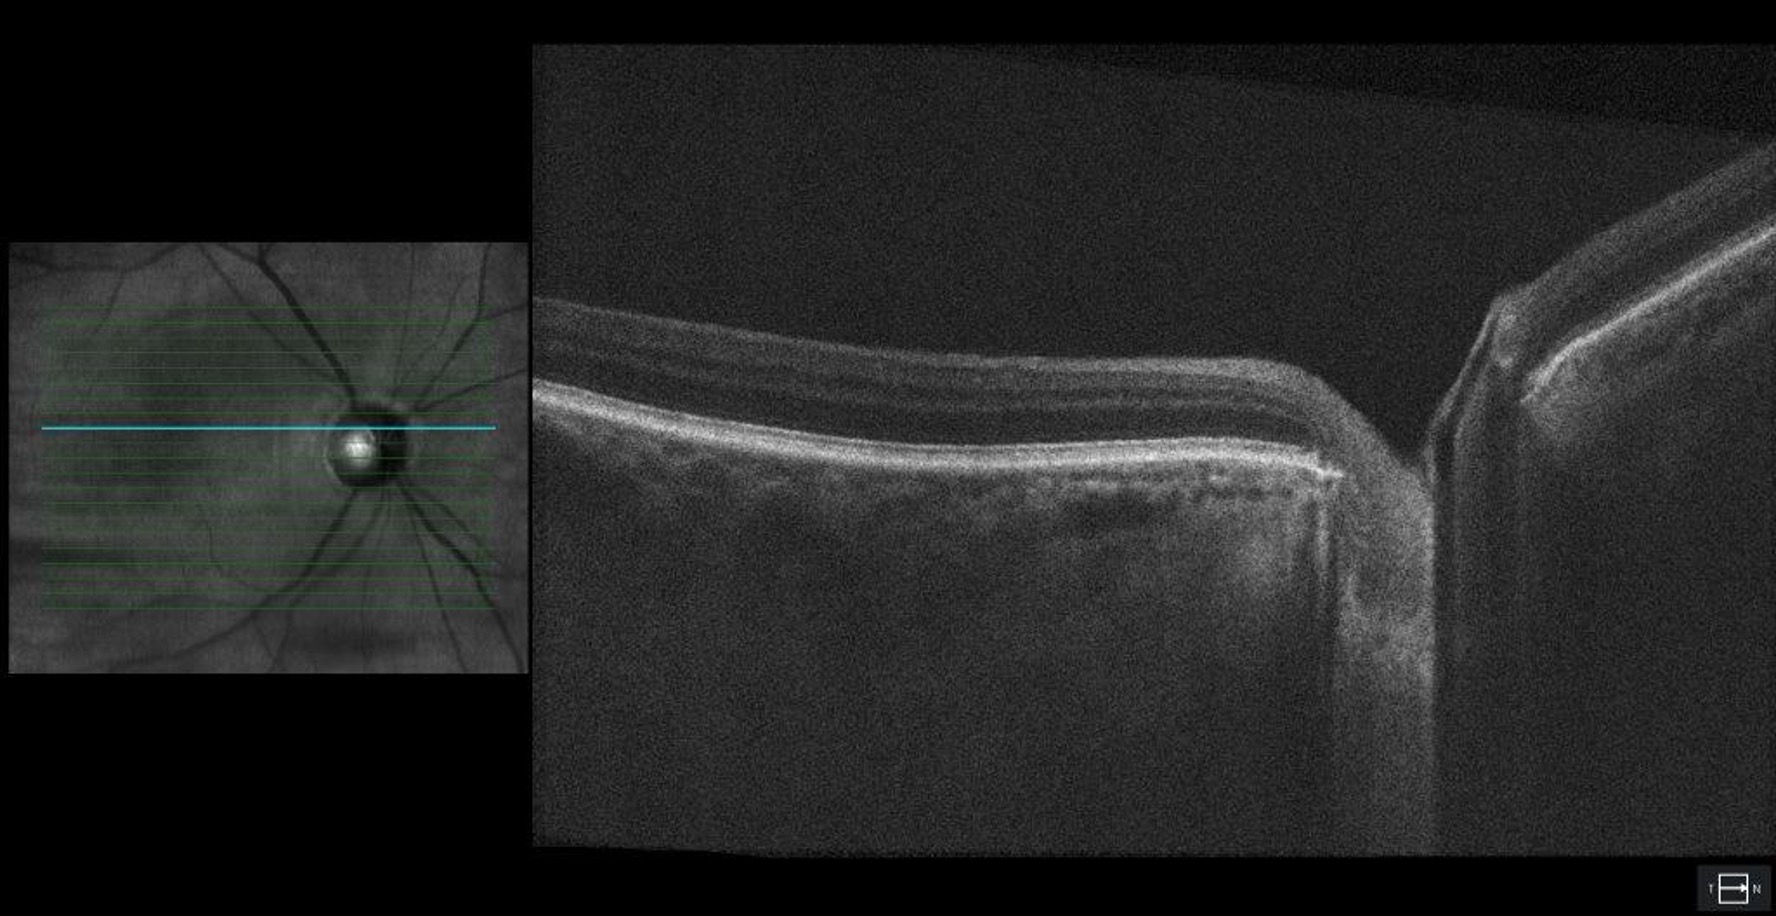

Optical coherence tomography (OCT) of the optic nerve head. Reduced retinal nerve fiber layer (RNFL) thickness in both eyes with an average RNFL thickness of 70 μm OD and 70 μm OS.

Figure 3. Optical coherence tomography (OCT) of the optic nerve head. Reduced retinal nerve fiber layer (RNFL) thickness in both eyes with an average RNFL thickness of 70 μm OD and 70 μm OS.

Optical coherence tomography (OCT) of the optic nerve head showing severe dropout of the ganglion cell complex (GCC) in both eyes. Average GCL thickness was 53 μm OD and 55 μm OS.

Figure 4. Optical coherence tomography (OCT) of the optic nerve head showing severe dropout of the ganglion cell complex (GCC) in both eyes. Average GCL thickness was 53 μm OD and 55 μm OS.